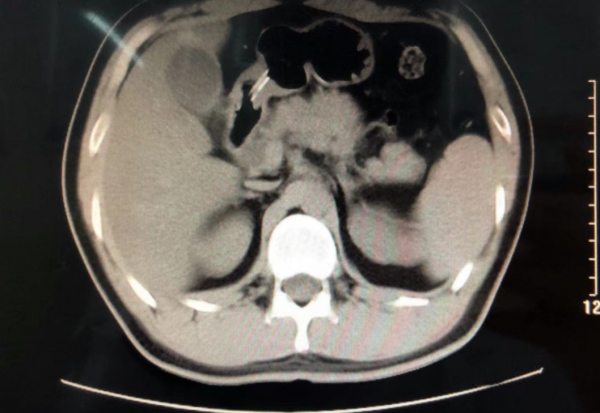

患者上腹部CT:胰腺體積增大,周圍滲出,胰管輕度擴張

患者就診時生命體徵,體溫36.0攝氏度,脈搏77次每分鐘,呼吸20次每分鐘,血壓113/76mmHg。輔助檢查:超敏C反應蛋白 1.12 mg/dl(正常值0.0-0.6),血脂肪酶 805.20 U/L(正常值0-60),血澱粉酶 232.70 U/L(正常值30-110),尿澱粉酶 1186.60 IU/L(正常值32-641)。上腹部CT示:脂肪肝;胰腺體積增大,周圍滲出,胰管輕度擴張。結合患者體徵表現以及輔助檢查,均提示患者急診胰腺炎診斷明確。 治療上立即給予持續胃腸減壓,生長抑素抑制胰腺外分泌,泮托拉唑鈉抑酸保護胃黏膜,10%葡萄糖、氯化鉀、複方氨基酸18AA等營養支援對症;同時給予中藥生大黃水灌腸、芒硝外敷腹部以洩熱通腑、行氣導滯等中醫治療。 9小時後患者腹痛症狀明顯減輕。隔日正常排便。第4日患者腹痛、腹脹的症狀消失,拔除胃管,經口食用稀飯、軟爛麵條等半流質飲食。第6日患者無不適症狀,複查血、尿澱粉酶均已經正常。